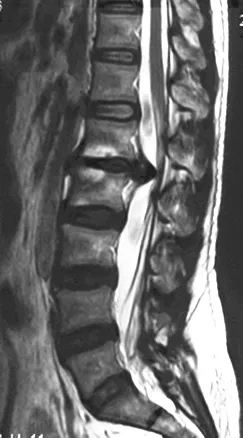

? 术前磁共振

据悉,来自安康市的女性患者因为长期久坐办公出现腰椎间盘突出症,在当地尝试多种保守治疗均无效,因为工作忙也没有进行系统化治疗。6月中旬工作劳累后,患者病情突然加重,腰部以及双下肢剧烈疼痛,伴有麻木和无力感,卧床无法下地。一天后大小便排便也出现困难。当地医院检查后诊断为腰椎间盘巨大突出,压迫神经程度严重,突出部位在脊髓圆锥部位手术风险大,术后恢复较差,建议到空军军医大学西京医院接受治疗。

入院时,患者卧床不能自理,双下肢剧烈疼痛让患者连续几个晚上睡觉都十分困难。查体显示双侧髂腰肌肌力II级,双侧股四头肌力III级,远端肌力轻度减低。鞍区感觉减退,肛门括约肌轻度松弛,小便费力。综合影像学检查结果诊断为腰1/2椎间盘脱出,马尾综合症。6月25日,在空军军医大学西京医院脊柱外科王哲主任安排下,丁坦副教授主刀实施腰1/2椎板切除减压,髓核摘除,椎间植骨融合内固定术,手术用时2小时顺利结束。